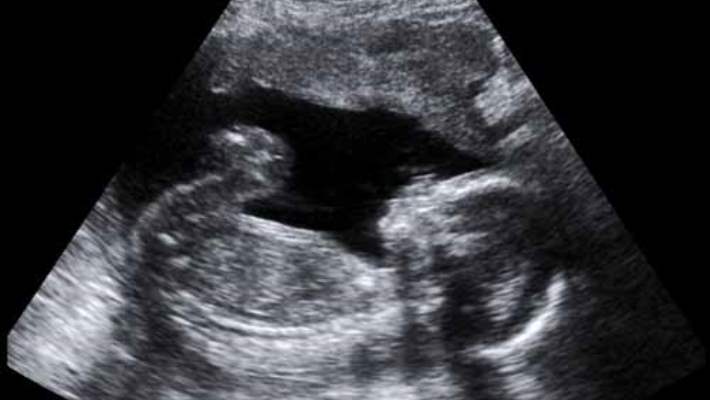

Araştırmaya imza atanlardan Katri Raikonen, hamilelikte tansiyonun yükselmesinin rahimde bazı değişikliklere yol açtığını ve bu değişikliklerin fetüste hayat boyu devam eden zeka sorunlarına neden olabileceğini belirtti.

Yüksek Tansiyon Bebeğin Zeka Gelişimini Etkiliyor